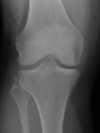

Not at all

2